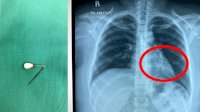

Waspada, Jarum Pentul Tertelan saat Pakai Hijab-Dikeluarkan dari Lambung